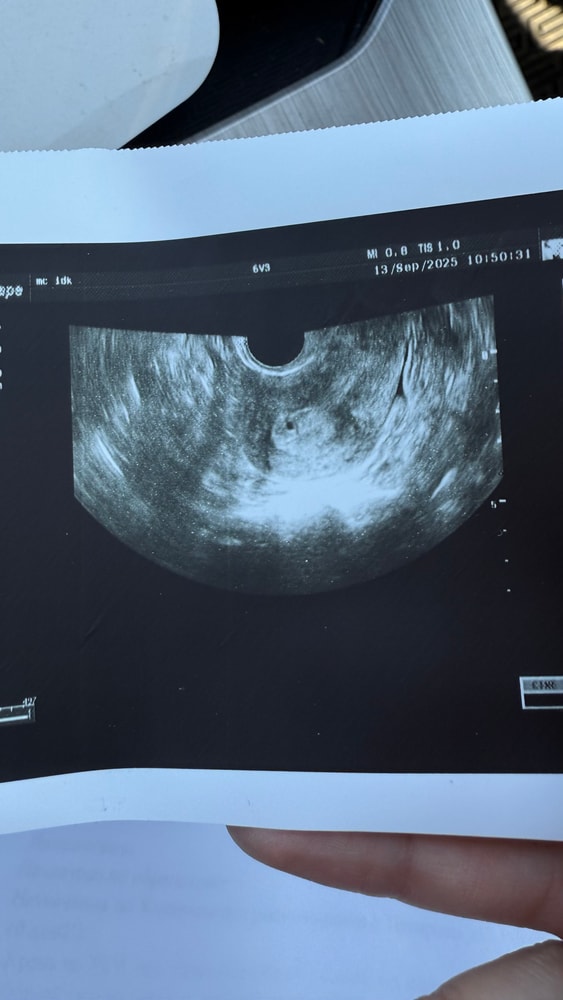

Девочки. Может так у кого-то было: до месячных неделя. Вчера начал покалывать яичник. Утром тоже самое. Поехала на узи: по узи плодное яйцо под?, в яичнике желтое тело, фолликулы. «Похожая картина беременности, нужно сдать хгч. Если отрицательно- пересдать через неделю, так возможно идет стадия прикрепления и поэтому хгч нет».

фото узи прикрепила